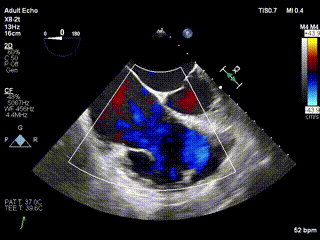

2021年12月24日,復旦大學附屬中山醫院葛均波院士團隊成功應用LuX-Valve Plus為一例極重度三尖瓣反流(TR)合并房顫、房缺的患者完成了經血管三尖瓣置換術,這是在前基礎上,本周完成的第三例經血管三尖瓣置換手術,葛均波院士、周達新教授等與心外科魏來教授、賴顥教授,心超室的潘翠珍教授、李偉教授及麻醉科的郭克芳教授共同完成了本周手術,均獲得圓滿成功!患者術后超聲顯示無TR,臨床癥狀明顯改善。本周手術的成功也為LuX-Valve Plus救治性臨床研究添上了濃墨重彩的一筆。

三例患者入院后,葛均波院士團隊周達新教授、潘文志教授、張源博士、陳莎莎博士及心超室的潘翠珍教授、李偉教授對患者的情況進行詳細評估和討論,最終決定為三例患者選擇LuX-Valve Plus40mm、50mm和50mm型號的瓣膜進行手術治療。手術后即刻拔除氣管插管,術后患者三尖瓣反流癥狀得到顯著改善,復查心超結果顯示人工三尖瓣瓣膜支架固定穩定,瓣葉關閉形態未見異常,未見明顯反流。